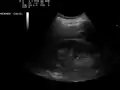

Ultrasound of liver (left side of the image) and right kidney (right side of the image) and Morison's pouch, not containing fluid.